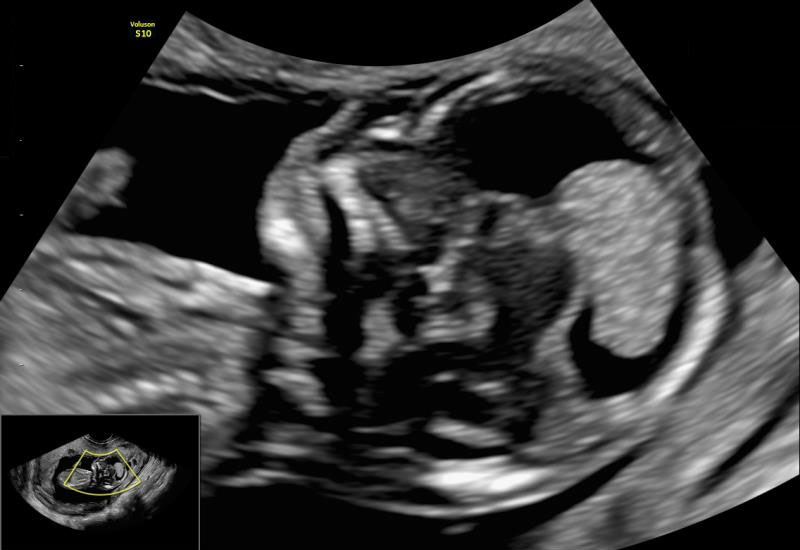

The Nuchal Translucency (NT) Scan is a specialized ultrasound performed in the first trimester of pregnancy to assess the risk of chromosomal abnormalities and certain structural conditions. This scan plays a crucial role in early fetal assessment and is conducted with high precision under the expertise of Dr. Ashwini Rathi, a certified Fetal Medicine Specialist.

The NT scan measures the thickness of a fluid-filled space at the back of the baby’s neck. An increased measurement may be associated with chromosomal disorders such as Down syndrome (Trisomy 21), Trisomy 18, Trisomy 13, single gene abnormalities, genetic syndromes and certain heart defects.

The NT Scan is performed between 11 weeks to 13 weeks and 6 days of pregnancy, when the measurement is most accurate and clinically meaningful.

- Nuchal translucency thickness

- Presence or absence of the nasal bone

- Early assessment of major structural anomalies

- Fetal heart rate

- Confirmation of gestational age

The scan is performed abdominally and always require a transvaginal approach for optimal visualization. It is a highly specialized ultrasound that requires strict adherence to international FMF guidelines for accuracy.